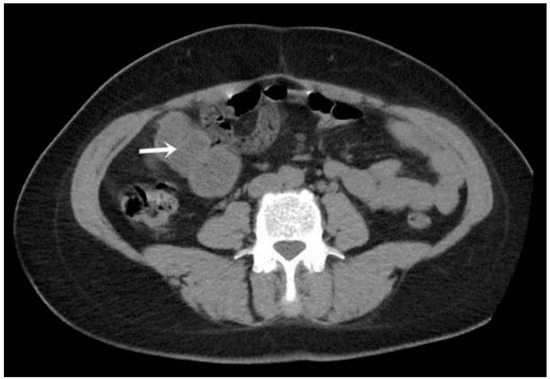

A CT examination revealed multiple cystic images in the hepatic segments V, VI, and VII, with subhepatic extension and involvement at the fissures of the venous ligament. Cystic images were also observed in the anterior abdominal wall and submesocolic (Figure 5, Figure 6, Figure 7, Figure 8 and Figure 9). Blood tests showed no significant abnormalities, and ELISA determination of IgG class antibodies to Echinococcus granulosus was positive at 1.66 IV (with values considered negative at ≤0.9 IV and positive at ≥1.1 IV).

The imaging highlights hepatic cysts in segments V, VI, and VII, a large cystic formation in the round ligament, a cyst in the parietal peritoneum, two cysts in the greater omentum, and two cysts located in the submesocolic enteral mesentery.

Figure 5. Omental hydatid cysts (indicated by arrows).